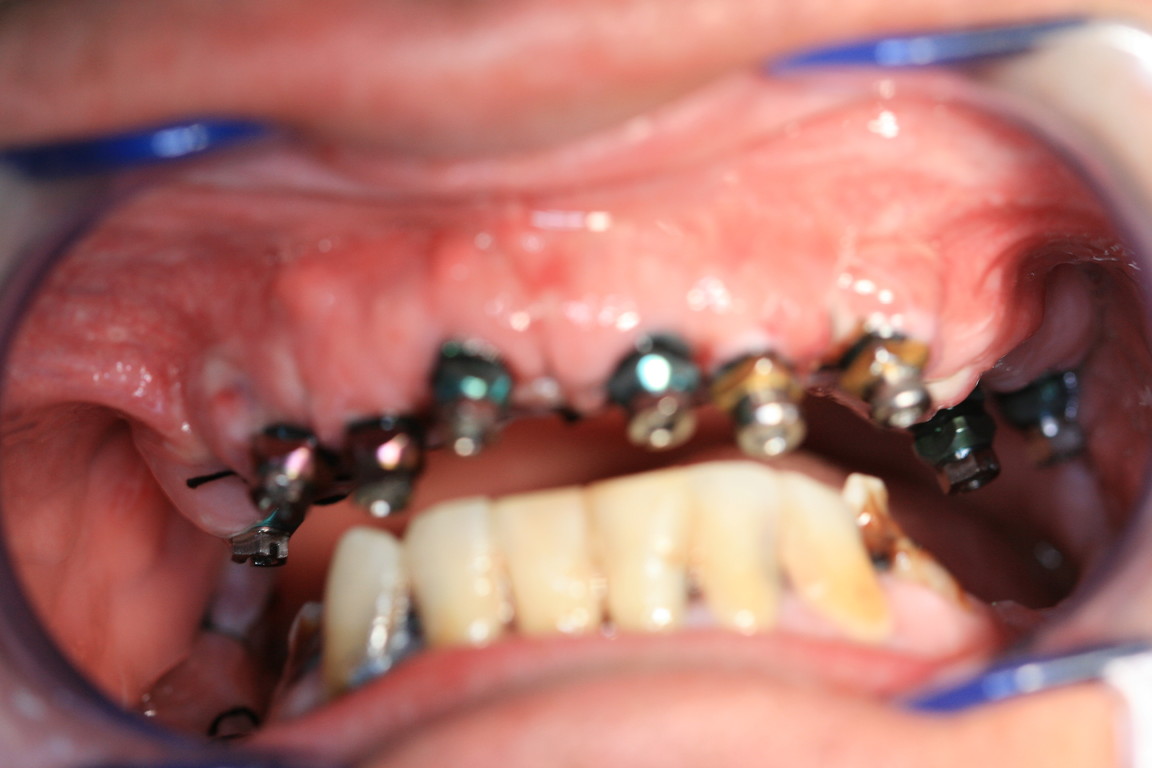

REHABILITACIÓN IMPLANTOSORTADA EN MANDÍBULA Y MAXILAR.